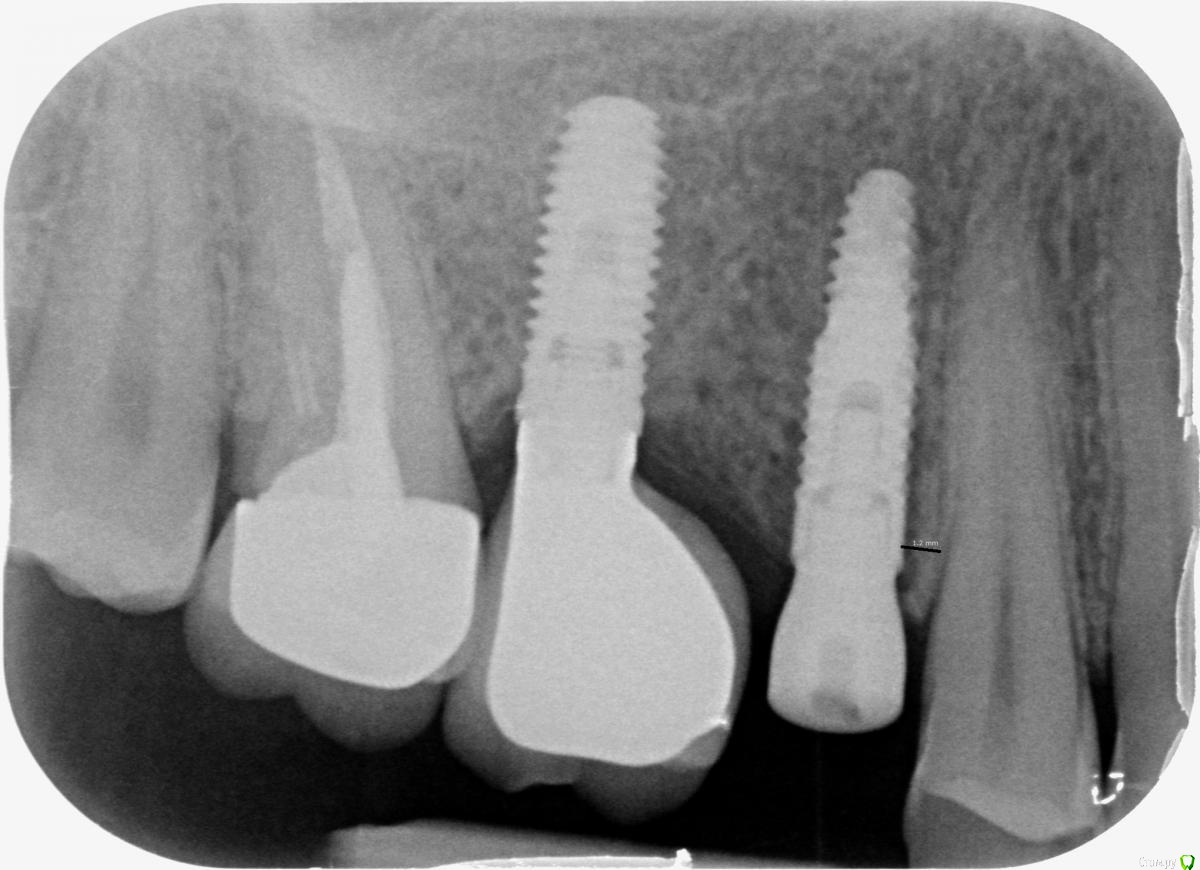

Галина Лазарева Опубликовано 9 ноября, 2015 Поделиться Опубликовано 9 ноября, 2015 Добрый день!06.11.15 врач поставил имплант фирмы "Semados" на верхнюю пятерку справа (1.5). Прописал Амоксиклав 1000 мг раз в сутки.На следующий день соседний зуб (1.4.) выдвинулся чуть вниз и при надавливании болит, при смыкании рта в прикусе чувствуется только этот зуб (1.4.).09.11.15 г сделали рентген.Врач предложил два варианта:1. подшлифовать здоровый зуб (1.4.) и подождать, пока спадет отек костной ткани.Я наобрез отказалась, т.к. трогать здоровый зуб считаю неправильным, и после спадения отека подшлифованный зуб выйдет из прикуса.2. подождать еще 2-3 дня, пока спадет отек, принимать неделю Амоксиклав 1000 мг 2 раза в сутки в течение недели, чтобы исключить возможное воспаление, которого сейчас нет. Для врача не проблема вынуть сейчас имплант и через полгода поставить его заново, но уже по центру, как надо.Вопрос в том, что врач считает, что имплант стоит нормально. В то же время, врач не исключает, что можно потерять из-за травмы (в результате близко посаженного импланта) свой живой соседний зуб (1.4).Если вынуть имплант сейчас, живой зуб, скорее всего, быстро прийдет в норму и не погибнет. Подскажите, пожалуйста, как поступить? Уж очень хочу сохранить свой живой зуб. Расстояние в 1 мм от соседнего зуба для импланта - это не мало? Может, не рисковать и не мучать себя антибиотиками, а вынуть имплант и поставить все через полгода по нормальному? Ссылка на комментарий

Большой Зеленый Опубликовано 9 ноября, 2015 Поделиться Опубликовано 9 ноября, 2015 Нормально стоит .Надо просто поменять формирователь десны на потоньше. Прищемляет немного.. 6 Ссылка на комментарий

doca Опубликовано 9 ноября, 2015 Поделиться Опубликовано 9 ноября, 2015 по снимку все нормально, принимайте антибиотики, как рекомендовал доктор. Ссылка на комментарий